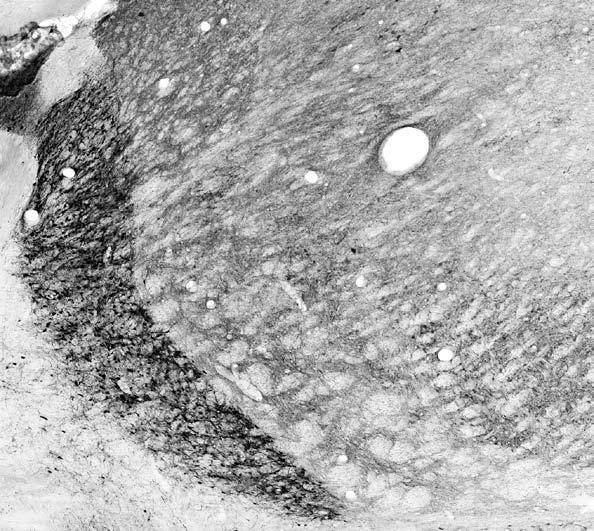

Supportive validation

- Submitted by

- Antibodies Incorporated / NeuroMab (provider)

- Main image

- Experimental details

- Adult rat thalamus immunohistochemistry.